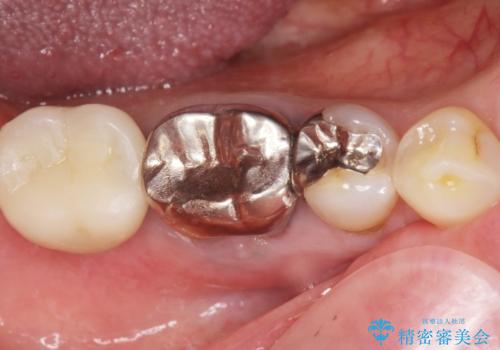

- 奥歯のインプラントをご希望し来院された患者様です。

骨が少なく下顎神経に近いことから、他院でインプラントできないと言われたとのことでした。

骨増生(GBR)を行い骨を増やすことでインプラント治療を可能にしました。